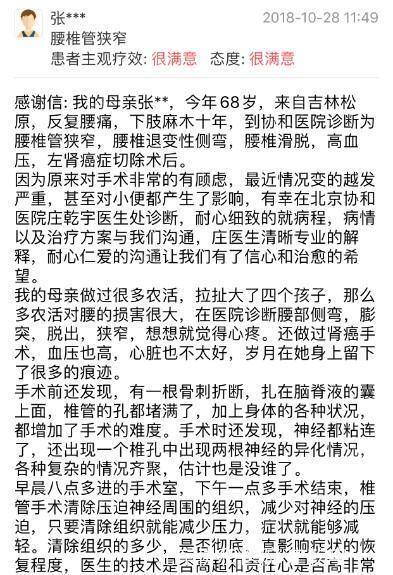

患者反复腰痛,下肢麻木十年,行走300米即出现明显双下肢酸痛麻木,无法行走,有典型间歇性跛行表现。

诊断为腰椎管狭窄,腰椎退变性侧弯,腰椎滑脱,高血压,左肾癌症切除术后。

考虑患者腰痛主要与腰椎滑脱、腰椎侧弯有关;下肢行走后酸胀疼痛主要与腰椎管狭窄症有关。

患者手术过程顺利,完全按照手术方案完成。通过一次手术解决了患者的腰椎管狭窄、腰椎侧弯和腰椎滑脱;虽然患者存在韧带骨化,硬膜压迫明显,但通过精细操作未出现脑脊液漏;术后患者腰痛及间歇性跛行的症状明显缓解,侧弯导致的外观异常和躯干偏移也明显矫正;术后X片可见腰椎侧弯及腰椎滑脱均得到满意的矫正。